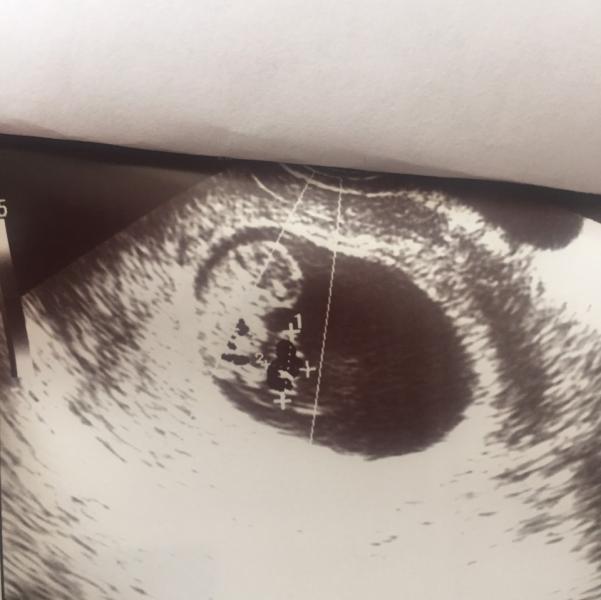

Сегодня рядом с эмбрионом обнаружили ещё "что-то" длинной в 1 см. Основной эмбрион 3 см!

Предполагают второй эмбрион,который не развивается( трап-синдром), киста, ещё что-то. Назначили повторное узи через неделю.

Напишите пожалуйста. Срок 9 недель.